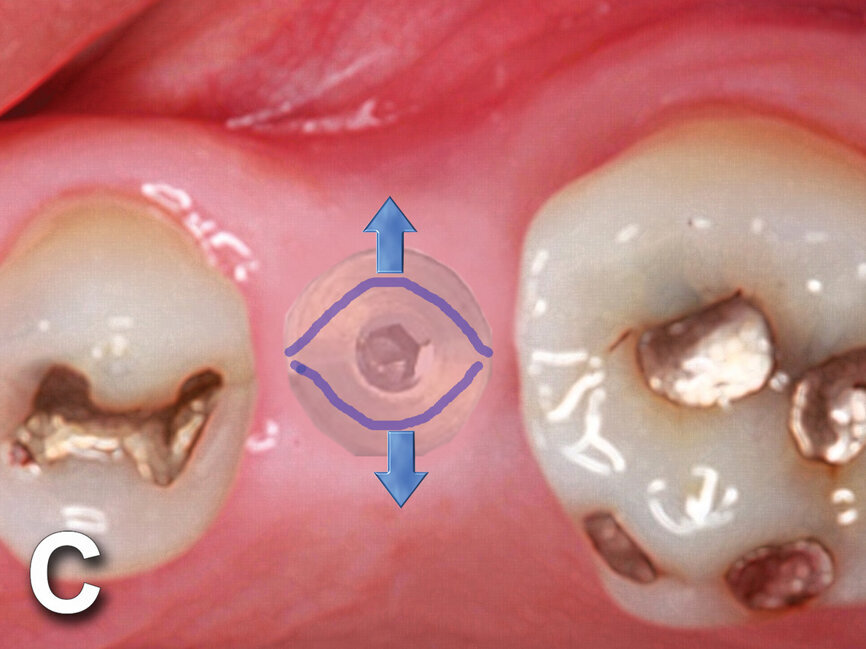

Figs. 4a: Implant to be uncovered (4a) presents with two options depending on width of attached gingiva available. Wide band of attached gingiva will remain after removal of tissue over cover screw, and the diode is utilized in a spiral pattern starting at center until fully exposed (4b). With the narrow band of attached gingiva present, an elliptical cut is made with the diode and tissue is pushed buccally and lingually to preserve the attached gingiva (4c). (Photo provided by Dr. Gregori M. Kurtzman)

Fig. 4b: Implant to be uncovered (4a) presents with two options depending on width of attached gingiva available. Wide band of attached gingiva will remain after removal of tissue over cover screw, and the diode is utilized in a spiral pattern starting at center until fully exposed (4b). With the narrow band of attached gingiva present, an elliptical cut is made with the diode and tissue is pushed buccally and lingually to preserve the attached gingiva (4c). (Photo provided by Dr. Gregori M. Kurtzman)

Fig. 4c: Implant to be uncovered (4a) presents with two options depending on width of attached gingiva available. Wide band of attached gingiva will remain after removal of tissue over cover screw, and the diode is utilized in a spiral pattern starting at center until fully exposed (4b). With the narrow band of attached gingiva present, an elliptical cut is made with the diode and tissue is pushed buccally and lingually to preserve the attached gingiva (4c). (Photo provided by Dr. Gregori M. Kurtzman)

The width of attached gingiva remaining will dictate the best method for implant uncovery (Fig. 4a). When a wide band of attached gingiva is present and a sufficient amount (3 mm or greater) will be present after uncovery on both the buccal and lingual, then the diode laser is activated and inserted at the center of the site and worked in a spiral pattern outward until the entire cover screw is exposed (Fig. 4b).

A curette or other instrument may be necessary to loosen the tissue over the cover screw as the periosteum becomes adherent to the titanium cover screw during implant healing. Sites that present with a narrow width of attached gingiva of 3-5 mm at the crest’s center will require some conservation of the remaining attached gingiva. In this clinical situation, the diode is utilized to remove an elliptical piece of soft tissue over the cover screw, and then the tissue is pushed buccally and lingually to preserve the attached gingiva (Fig. 4c).